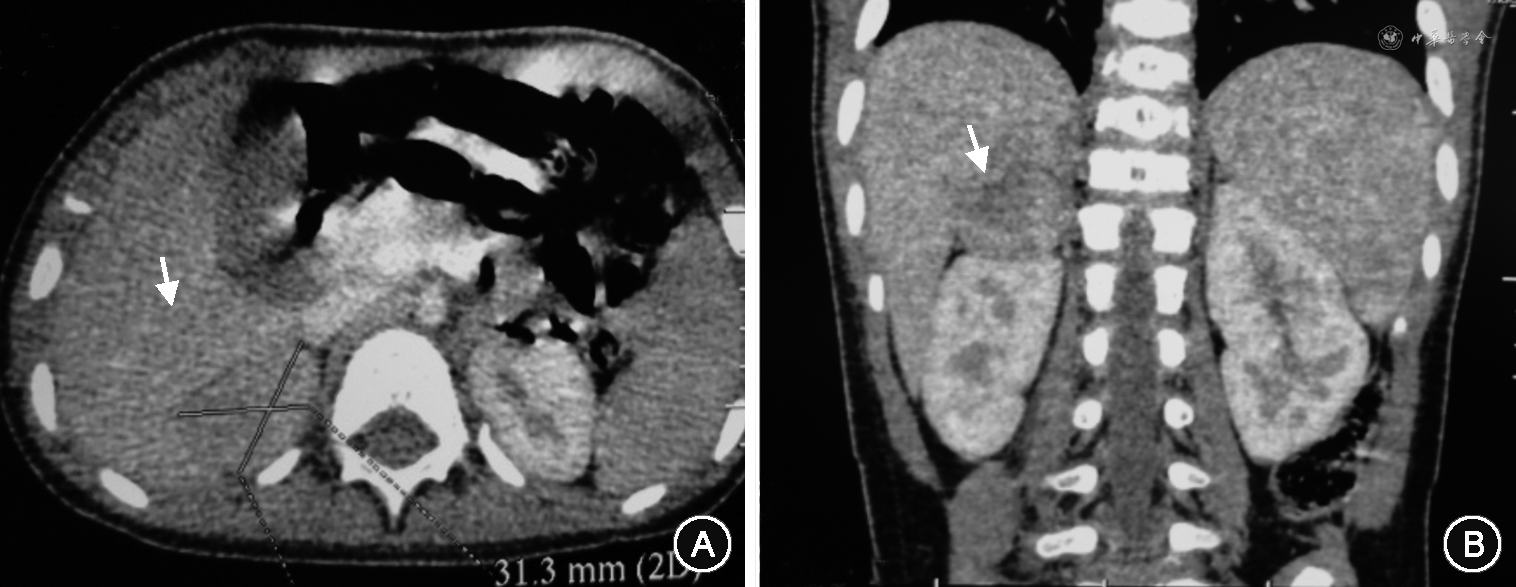

为进一步判断雄激素来源,行中剂量地塞米松抑制试验:对照为睾酮2.19 nmol/L,17α-OHP 0.87 μg/L;服药后睾酮2.01 nmol/L,17α-OHP 0.69 μg/L,提示高雄激素未被抑制,且17α-OHP不高。进一步CYP21A2基因检测结果回报阴性,肾上腺B超及CT见右侧肾上腺实性占位,大小4.7 cm×3.1 cm×3.1 cm,边界清,分叶状,其内丰富血流信号,考虑右侧肾上腺皮质肿瘤(图1)。盆腔B超符合幼稚子宫,右附件区囊肿。2012年8月在北京儿童医院行肾上腺肿物切除术,术后肿块病理检查:大小4 cm×3 cm×2 cm,重20 g,切面实性,结节状。免疫组化:Syn+,CgA-,MelanA-,Vim+,钙网膜蛋白+,抑制素+,S100-,EMA-,Ki67 8%。考虑右肾上腺皮质腺瘤,且生长活跃。术后复查:睾酮0 nmol/L,孕酮0 μg/L,血皮质醇176.3 μg/L。查体:嗓音较前变细,阴毛3期,阴蒂增大较前好转,长度约1 cm。其后患儿规律随诊至2020年8月(9岁7个月),睾酮水平一直稳定在正常范围,但骨龄始终超过实际年龄。2018年10月(8岁9个月)查雌二醇 28.02 ng/L,睾酮1.11 nmol/L,骨龄相提示11岁,为减少对患儿终身高的影响,开始口服来曲唑 2.5 mg/次,隔日1次。2020年4月因乳房发育停用来曲唑。2020年8月患儿于本院随诊,查体:身高152.5 cm(>同年龄同性别健康儿童身高P97),体重41 kg,肤色稍黑。乳房2期,阴毛2~3期。肾上腺CT提示右侧肾上腺区术后改变,复查睾酮0.867 nmol/L。